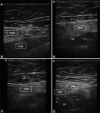

Methods: After general anaesthesia or spinal anaesthesia administration and before surgical incision, 80 patients undergoing TKA were randomised into group TIPS (received ultrasound-guided TIPS block where 40 ml 0.25% bupivacaine and 4 mg dexamethasone were injected: 10 ml at the distal femoral triangle, 10 ml above the sartorius and 20 ml at the distal adductor canal) and group FNB (femoral nerve block; received ultrasound-guided FNB with 20 ml 0.25% bupivacaine mixed with 4 mg dexamethasone). Postoperative pain score was noted and compared.

Figures